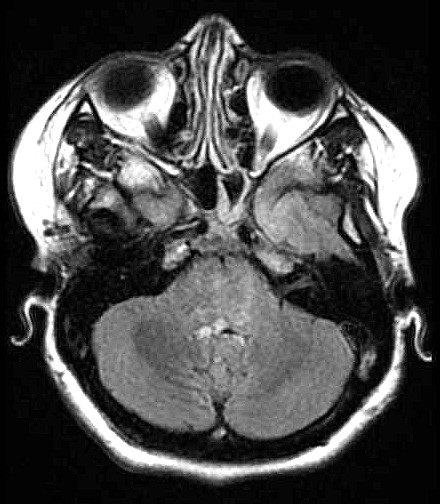

| Fem. 17a. |

| Nódulo sólido homogêneo preenchendo o III ventrículo, com limites precisos, com hipossinal em T1 e hipersinal em T2 e FLAIR, que se impregna por contraste paramagnético. Lesão menor implantada no assoalho do IV ventrículo provavelmente representa disseminação por via liquórica. |

| F. 17a. Tumor teratóide rabdóide atípico de III ventrículo. RM | HE | VIM, GFAP | HHF35, desmina, 1A4 | AE1AE3, EMA |